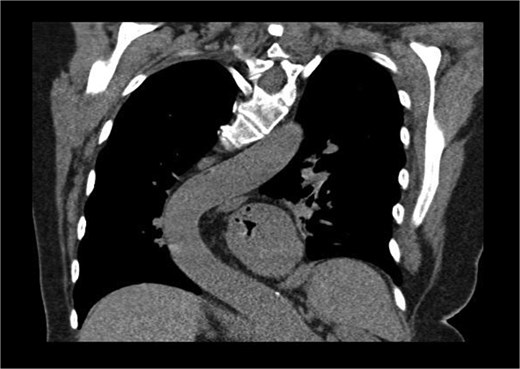

Preoperative imaging highlighted this significant spinal deformity and its impact on cardiac orientation and accessibility (Fig. 3). The scoliosis increased the complexity of the surgery, necessitating customized operative strategies. The patient underwent minimally invasive MVR and septal myectomy through a right mini thoracotomy. A mechanical valve was selected as a redo would be near impossible due to the cases uniqueness and inherent difficulty. Operative technique involved a 5 cm skin incision on the right upper breast at the 2nd ICS for a working port (Fig. 4), with additional ports in the 2nd and 4th ICS for camera and CO₂ venting. Extracorporeal circulation was established via femoral–femoral bypass through a groin incision to access the left femoral vessels for cannulation.